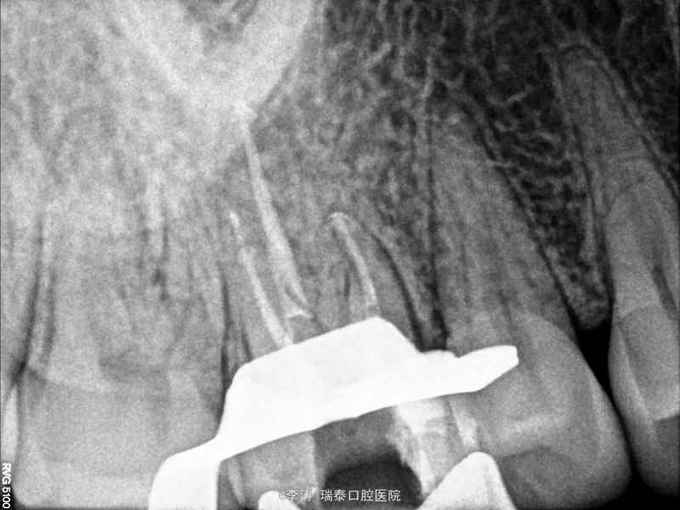

16牙合面大面积充填物,x线片根充不完善,根尖未见明显暗影

行16牙根管再治疗,嵌体修复